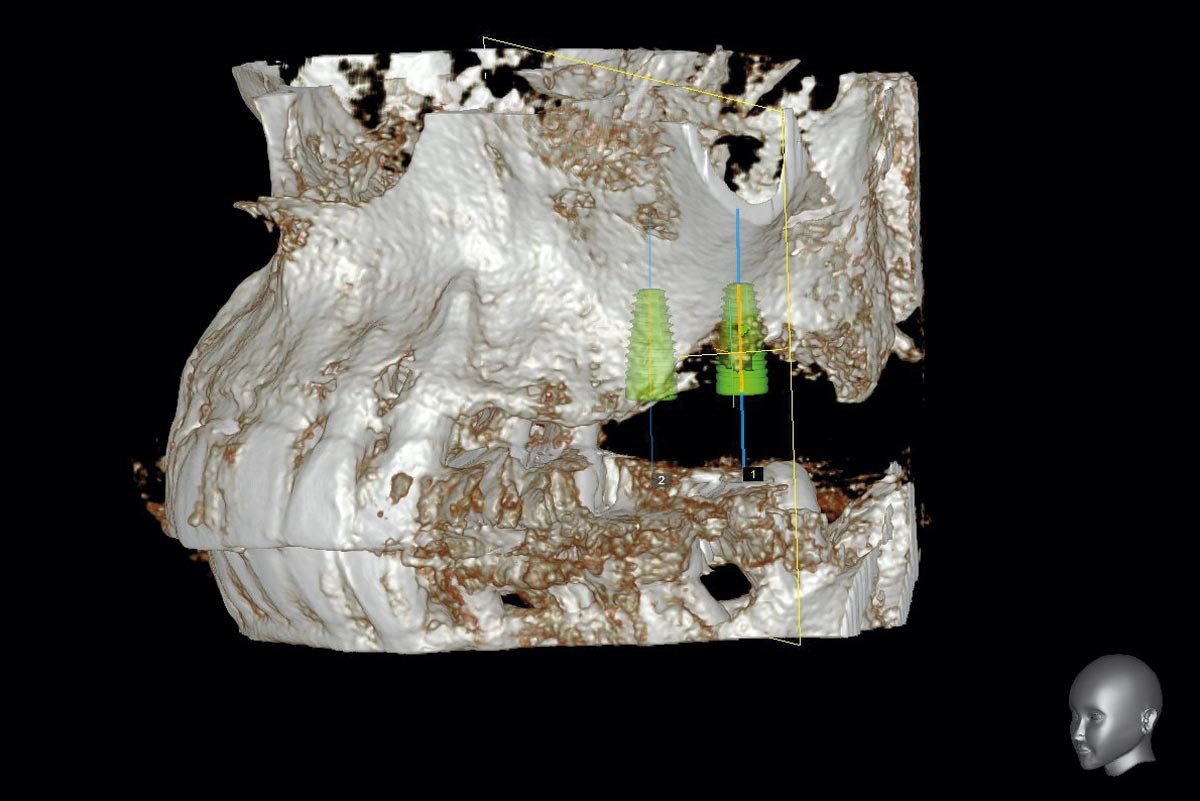

3/15 - Preoperative OPG - planning of the implant placementTreatment of a combined horizontal and vertical bone defect in the maxilla with maxgraft® cortico in the allogenic shell technique - Dr. R. Würdinger